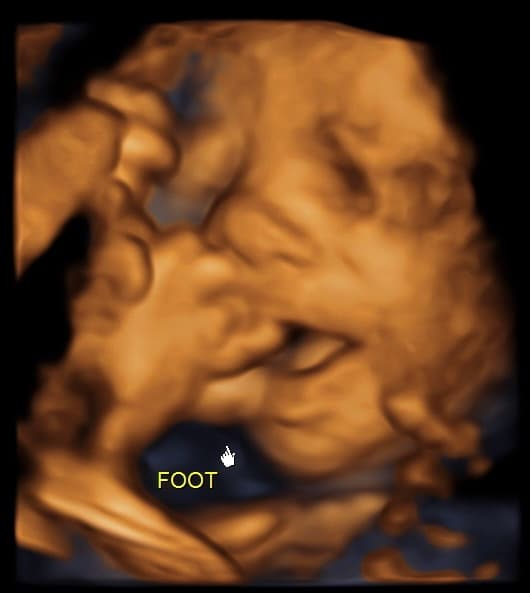

At Magnolia Fetal Imaging, we provide a warm, relaxing environment where you can bond with your baby through advanced 3D/4D & HD ultrasound technology. Our studio focuses on capturing precious keepsake moments for families — gender reveals, early looks, and high‑definition images you will cherish for a lifetime.

All sessions are non‑diagnostic and designed purely for bonding and keepsake entertainment.